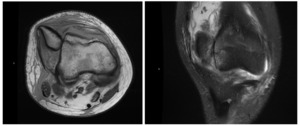

A 13-year-old adolescent girl, with a history of developmental delay and left knee patellar instability, presented to the emergency department 4 days after an injury to the right knee. The patient reported a fall from standing directly onto the anteromedial aspect of the right knee on a carpeted floor, resulting in immediate pain and swelling. Per the patient and her family, this was her first reported lifetime patellar dislocation of her right knee. At the time of presentation to the emergency department, the patient reported no pain with sitting, but significant pain with weight bearing and reduced range of motion of the right knee. Radiographs demonstrated a laterally dislocated patella (Figure 1). After several failed attempts at closed reduction, the patient was placed in a knee immobilizer and was urgently referred to the orthopedic clinic. For unknown circumstances, the patient did not present to our clinic until 10 days after sustaining the injury to her right knee. Magnetic resonance imaging was obtained, which was significant for a fixed lateral dislocation and rotation about the vertical axis of the right patella (Figure 2). The magnetic resonance imaging also showed attenuated medial patellofemoral ligament (MPFL) with high-grade/complete tearing towards the patellar attachment. On physical examination, the patient had pain with 90 degrees of flexion, crepitus with both flexion and extension, and a visible gross deformity at the lateral aspect of the knee. No numbness, tingling, or loss of sensation was noted. Discussion was had with the family regarding the need to proceed with surgical intervention and a plan was made for general anesthesia and open reduction of the fixed patellar dislocation with medial repair vs reconstruction. In general, MPFL reconstruction requires additional surgery including suture anchors and interference screws to be placed in the bone as well as a graft from either the patient or a donor. There is also additional time following these procedures for recovery. In this case, given this patient’s significant developmental delay, the family wished to move forward with medial repair because this was a more simple and straightforward surgery.